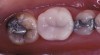

Fig 1. Bite impression tray with medium-viscosity VPS impression material before tooth preparation for crown for tooth No. 30; this impression is to be used for a matrix/stent for fabrication of a provisional crown.

Figure 1

Fig 2. Impression of crown before tooth No. 30 preparation.

Figure 2